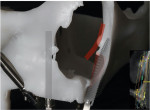

As an alternative to the quad zygoma technique, the transnasal implant technique was developed, in which implants are inserted into the basal bone of the maxilla, across the nasal cavity tangent to the distal wall, and anchored apically in the frontal process of the maxilla (Figure 1 and Figure 2).4,10,11 Using the nasal cavity walls as anchorage for implants12 increases bone availability in the anterior region of the maxilla, allowing for the installation of an anterior extra-long conventional implant accompanied by a posterior zygomatic implant (Figure 3). As long as the anatomy of the region is respected and the final positioning of the transnasal implants is appropriately planned, this technique has been shown to achieve a high success rate.11

The height of the alveolar ridge, the shape of the nasal cavity, and the availability of implant anchorage in the frontal process of the maxilla should be evaluated to determine if the transnasal technique is indicated, and the use of a prototype permits these criteria to be observed with greater security (Figure 4).18 The frontomaxillary pillar is found in a region where dense bone normally exists, which allows the placement of long implants with parasinusal angulation.19 Using these bone pillars as anchorage for dental implants transfixing the nasal cavity18 increases bone availability in the anterior region of the maxilla.